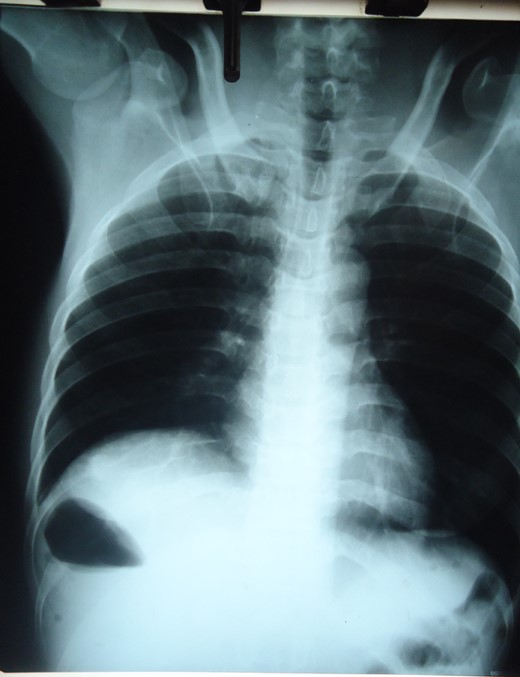

Plain abdominal X-ray showing distended small bowel loops and right sub-diaphragmatic shadow with air fluid levels from trapped bowel.

Small intestinal volvulus presents with severe colicky abdominal pains and vomiting that is difficult to differentiate from non-strangulating causes of intestinal obstruction. Early diagnosis and operative intervention is important to prevent gangrene seen in more than 40% of cases [3]. Mortality rates of 5.8–8% increases to 20–100% with gangrene [7]. Abdominal CT especially Multidetector CT with angiography is the most specific investigation [8]. Doppler ultrasonography showing the whirlpool sign is useful but operator dependent [9]. Plain radiography is insensitive in most cases. The plain radiographs of our patient showed a significant gas shadow below the right hemi-diaphragm that was discovered to be from entrapped bowel between the liver and diaphragm. An abdominal CT though more specific was omitted to minimize delay in the management. Radiological sign of hepato-diaphragmatic interposition of bowel loops was first described by Demitrus Chilaiditi in 1910 but the appearance in this patient differs from previous descriptions. Cases of Chilaiditi's syndrome have been reported in association with Fitz-Hugh-Curtis syndrome in large intestinal obstruction but none with small intestinal volvulus [10]. Treatment of small intestinal volvulus is derotation of the affected loop when viable and resection of gangrenous segments. Associated anatomical abnormalities are corrected by closure of intra-peritoneal defects, adhesiolysis or excision of mass lesions.